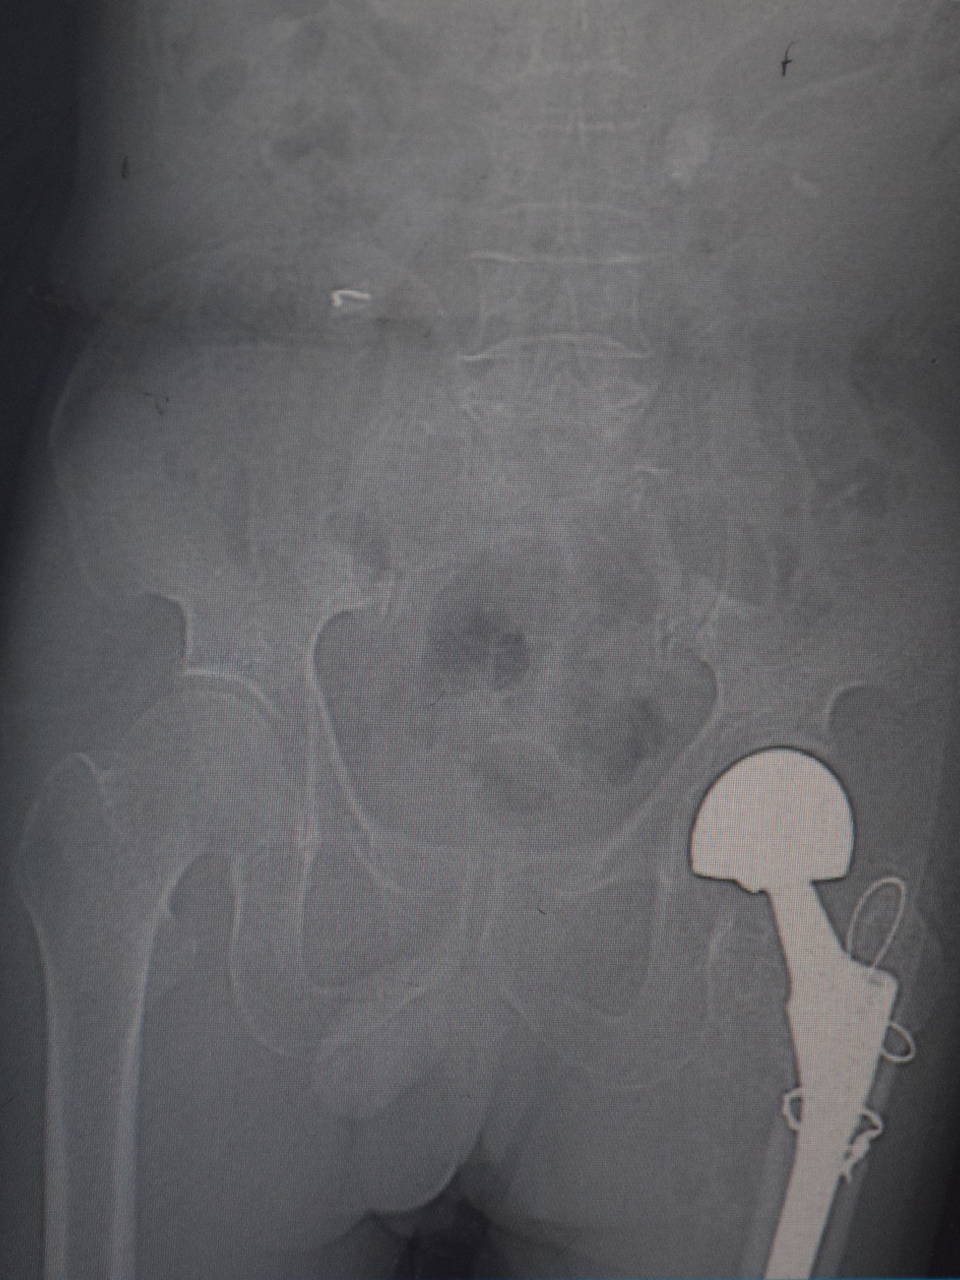

早在18年10月份,大爷因左腿髋关节股骨粗隆间骨折,在台州市博爱医院做了人工骨头置换,也是陈医生做的手术。大爷身体健朗,手术恢复的很好,不久也就在医院的安排下出院了。

关节影像